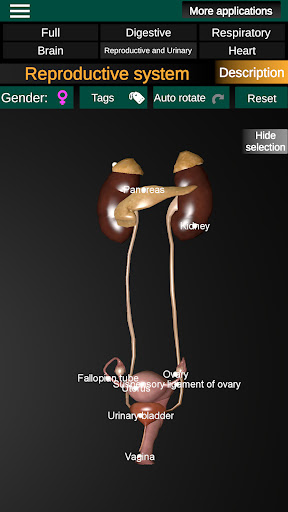

* Voortplantingssysteem, dat de mannelijke en vrouwelijke voortplantingsorganen omvat.

* Vergelijk mannelijke en vrouwelijke organen.

* Beschrijvingen van elk orgel.